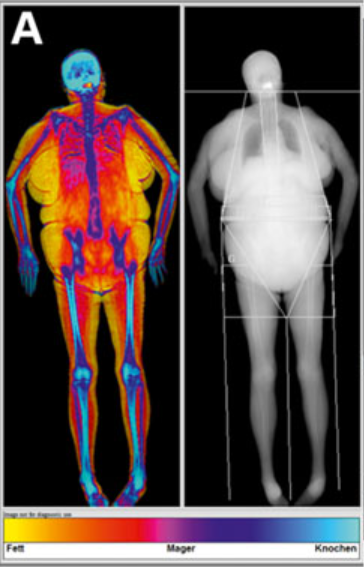

Abstract